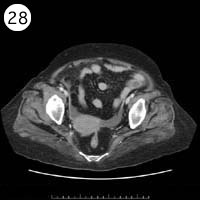

28

57歳 女性